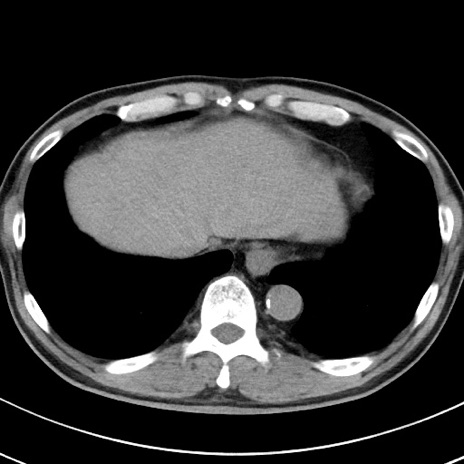

【腹部TIPS】症例29 参考症例 CT(横断像)

症例

70歳代男性